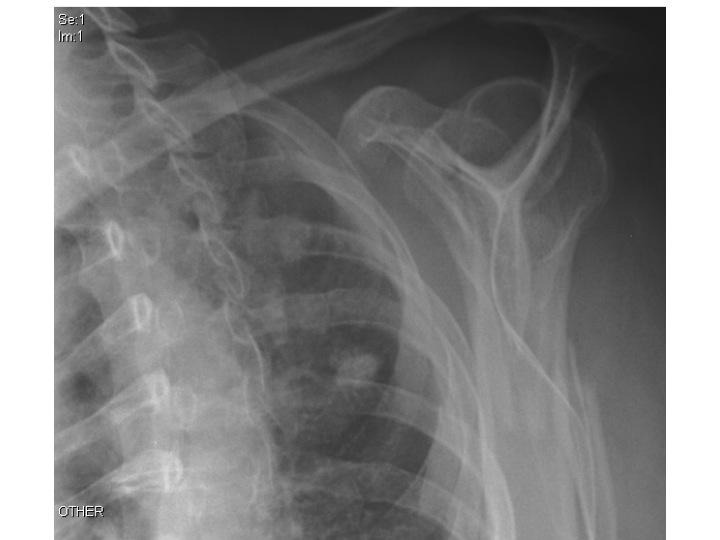

77 year old female complains of pain when she moves her left shoulder after falling down five stairs. What's the diagnosis, management, and other common associated injuries?